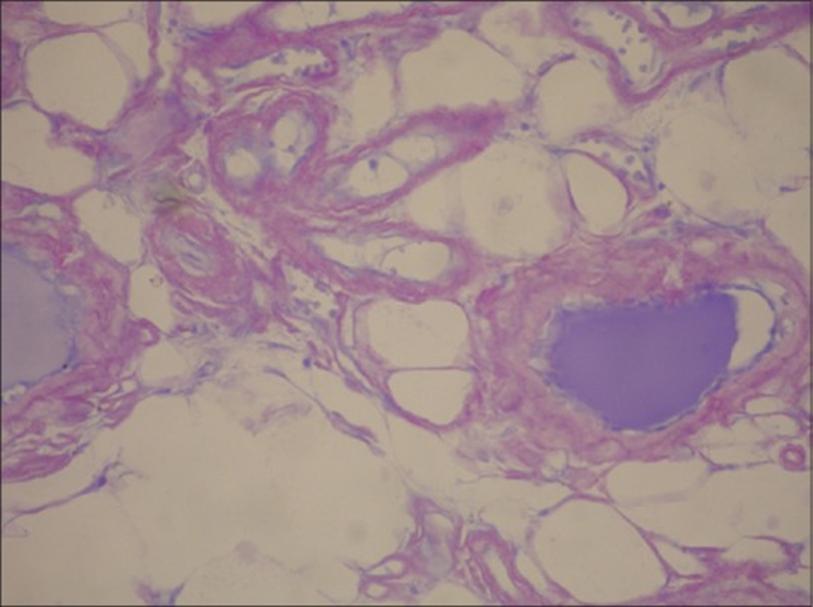

患者存在大量结节,行甲状腺全切除术。病理可见:右叶为12cm×7.5cm×7cm,左叶为9.6cm×6cm×5cm,包膜完整。在右叶切片中,发现一个4cm×3cm大小的部分囊性结节,边界清。左叶可见1个4cm×4cm大小的囊性结节。周围甲状腺组织硬化,呈浅棕色,外观均匀。镜检内含胶状物质的甲状腺滤泡增大、延长,滤泡及血管周围广泛聚集嗜酸性、无结构、不定形的淀粉样物质,滤泡和血管周围可见淀粉样物质积聚(见图1)。结晶紫染色切片可见甲状腺滤泡和血管之间弥漫性异染物质(见图2)。

刚果红染色偏振光显微镜检查呈绿色双折光。